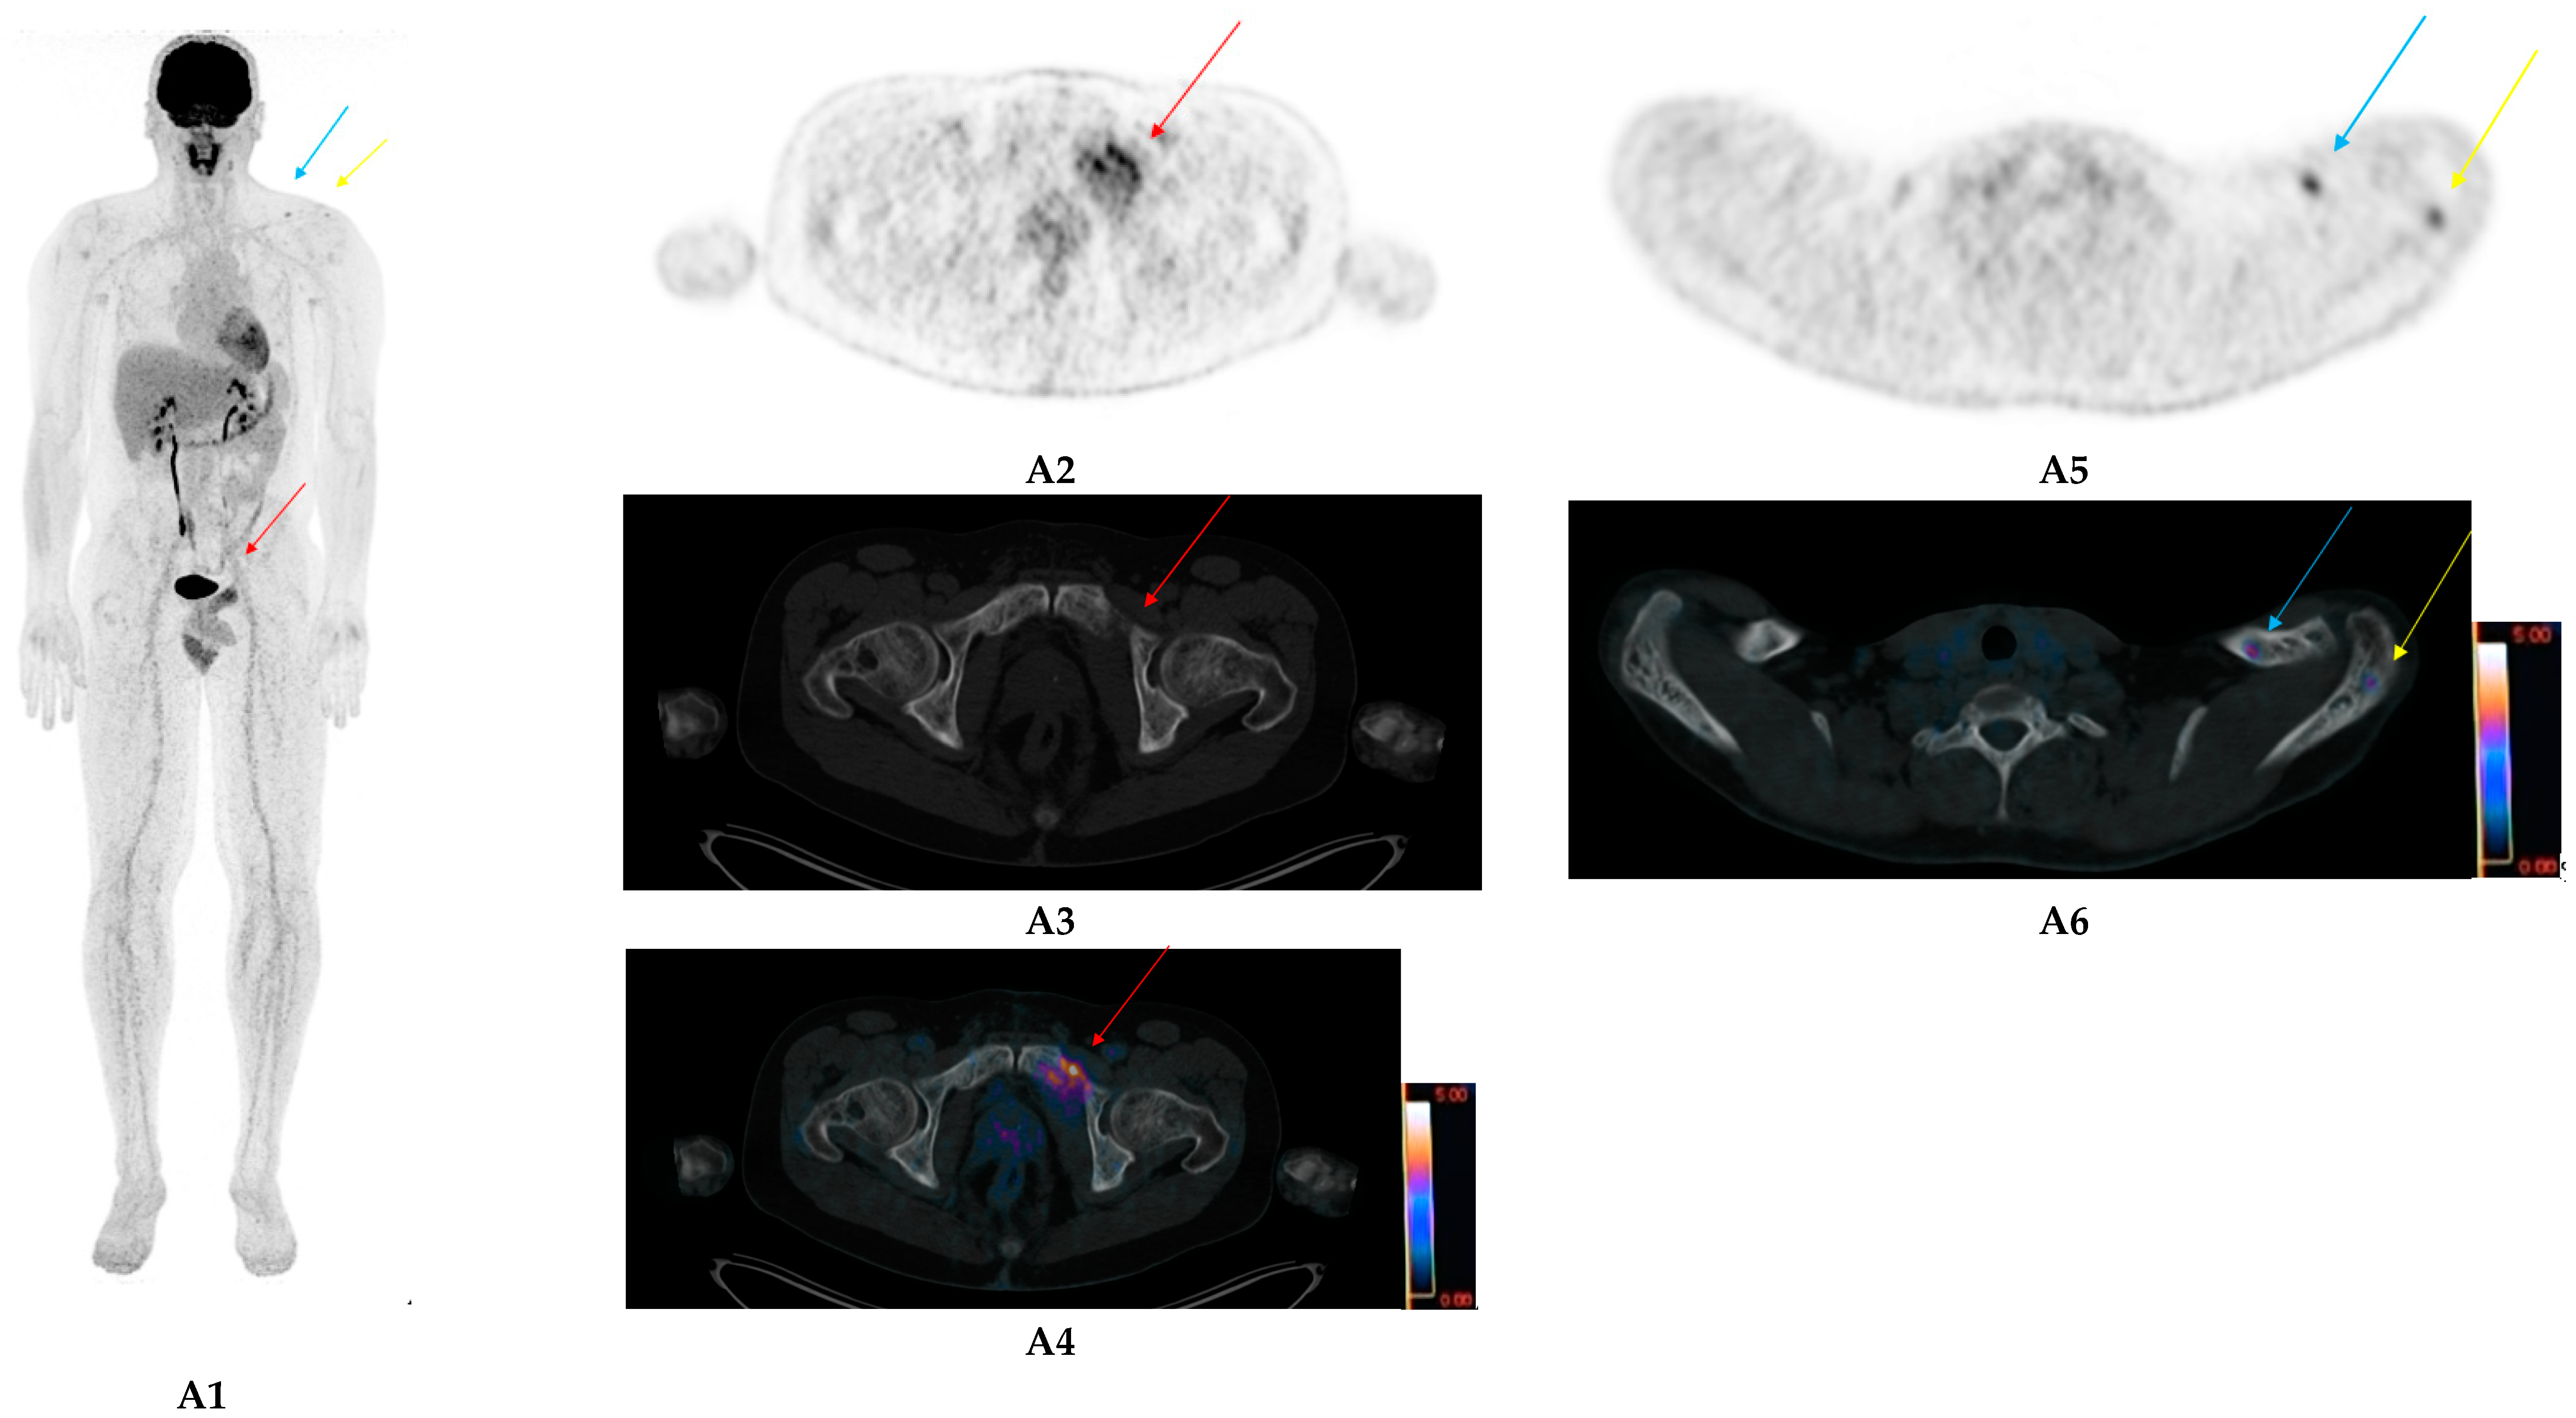

- Lapa, C.; Schreder, M.; Schirbel, A.; Samnick, S.; Kortüm, K.M.; Herrmann, K.; Kropf, S.; Einsele, H.; Buck, A.K.; Wester, H.-J.; et al. [68Ga]Pentixafor-PET/CT for imaging of chemokine receptor CXCR4 expression in multiple myeloma—Comparison to [18F]FDG and laboratory values. Theranostics 2017, 7, 205–212. [Google Scholar] [CrossRef]

- Pan, Q.; Cao, X.; Luo, Y.; Li, J.; Feng, J.; Li, F. Chemokine receptor-4 targeted PET/CT with 68Ga-Pentixafor in assessment of newly diagnosed multiple myeloma: Comparison to 18F-FDG PET/CT. Eur. J. Nucl. Med. Mol. Imaging 2019, 47, 537–546. [Google Scholar] [CrossRef]